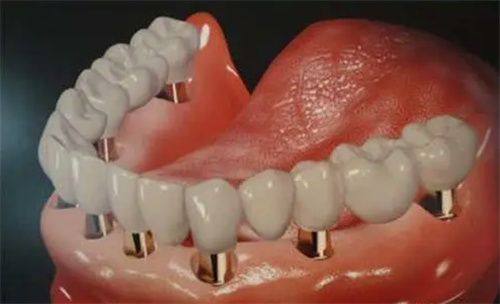

多颗及全口种植牙报价情况

多颗种植牙的价格主要与种植体数目和牙位数有关。需要种植的牙齿越多,费用自然也就越高。全口种植的价格跨度较大,在数十万之间,一般不超过50万元。

对于多颗牙缺失的患者,医生会根据具体的口腔情况制定个性化的种植方案。在这个过程中,种植体的数量和牙冠的选择都会影响更终的种植牙报价。全口种植牙是一项较为复杂的口腔修复项目,它不仅需要考虑种植体的稳定性和功能性,还需要关注美观度和舒适度。因此,全口种植牙的价格相对较高。